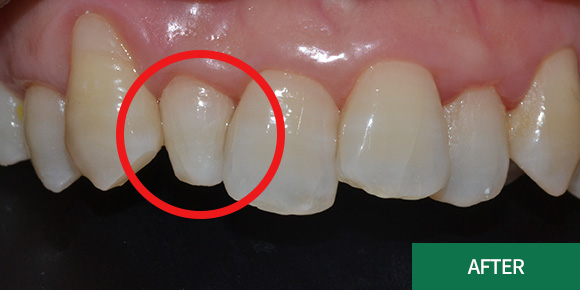

치경부마모증

치아의 옆 잇몸과의 경계부분이 패이면서

시린 증상이

발생하는 것을 치경부마모증이라고 합니다.

시린 증상이 있으시다면 진단받아보시는 것을

권장드립니다.